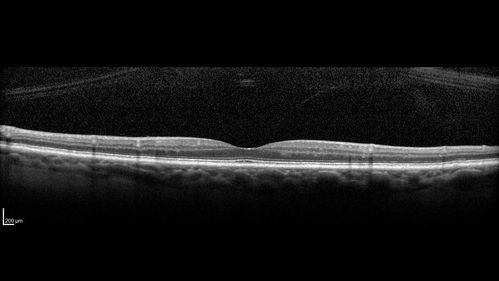

Stellate non-hereditary idiopathic foveomacular retinoschisis (SNIFR) and optic nerve drusen

84 year old man No visual complaints. Not diabetic, cataract surgery 8 years ago. Meds: Omeprazole, Tamsulosin (Flomax)

VA 20/32 OD, 20/20 OS